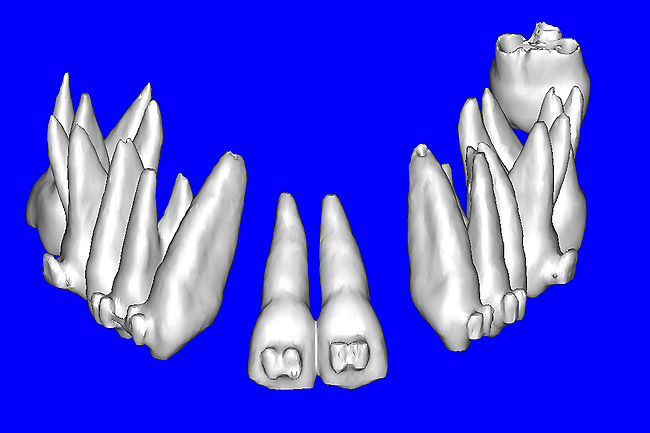

Using different masking (segmentation) and threshold Hounsfield unit values, several new 3D bone volumes can be created which offer invaluable information. To help determine the final position of each implant a new bone model was created with a Hounsfield unit value of 1480, which eliminated all but the densest objects included in the scan data. (Results may vary depending on the CBCT machine used.) The inner and outer layers of bone were removed, leaving the underlying enamel and root structure of the teeth (Figure 8A). After the bone had been stripped away, the root inclinations were examined closely. The most striking findings confirmed the rotated position of the right central, while revealing the slight mesial dilaceration of the root apex, which converged on the space needed for the path of the potential implant (Figure 8B). The schematic shapes of the proposed implants were visualized for the right and left lateral spaces in different rotations of the 3D maxillary arch. It was at this point that a determination was made as to the appropriate implant shape and type that would fit the available space while avoiding encroachment on adjacent tooth roots. A tapered design implant (Tapered Screw-Vent®, Zimmer Dental, www.zimmerdental.com) was chosen from the large virtual library. With the SIMPlant software, the virtual library contains data from dozens of implant manufacturers and realistic.computer-aided design representations as seen in Figure 9A through the translucent bone. The position of the left implant can be visualized with adequate mesial-distal distance between adjacent tooth roots (Figure 9B) and a more delicate placement (Figure 9C).

Figure 8a  By using the masking feature, the inner and outer layers of bone were removed virtually, revealing (A) the enamel and root structure of the teeth and the rotated position of the right central and (B) a slight mesial dilacerations of the root apex.

Figure 8a

Figure 8b  By using the masking feature, the inner and outer layers of bone were removed virtually, revealing (A) the enamel and root structure of the teeth and the rotated position of the right central and (B) a slight mesial dilacerations of the root apex.

Figure 8b

Figure 9a  Virtual implants were placed to determine the appropriate shape and type for the available space, in this case a tapered design allowed for adequate mesial-distal distance between adjacent roots.

Figure 9a

Figure 9b  Virtual implants were placed to determine the appropriate shape and type for the available space, in this case a tapered design allowed for adequate mesial-distal distance between adjacent roots.

Figure 9b

Figure 9c  Virtual implants were placed to determine the appropriate shape and type for the available space, in this case a tapered design allowed for adequate mesial-distal distance between adjacent roots.

Figure 9c